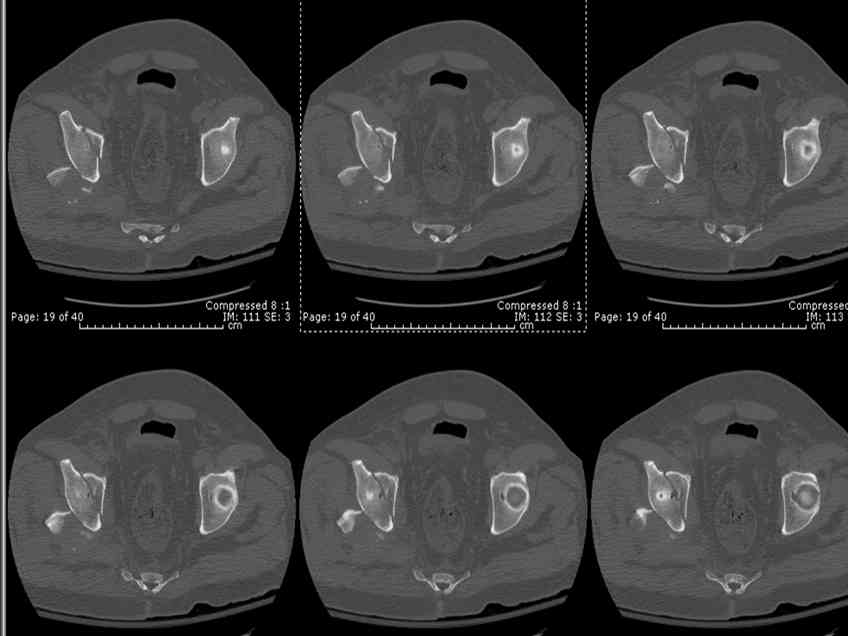

45 yo male in MVA, only other injury=small subarrachnoid bleed (neurologically fine, GCS never <14), with this transverse & associated posterior wall fx-dislocation 7/7

Pt has a history of prior abdominal surgery in Colombia (gastric bypass for obesity -- now <200 lbs).

In skeletal traction thru distal femoral pin 40 lbs with decent reduction - except for the free fragments in the hip joint. ORIF planned for post-injury day 11.

Biggest problem appears to be impaction & comminution of the posterior wall fx site - you've left out some CT cuts. This is not just fragments in joint. It may leave a deficient area, &/or block satisfactory posterior wall reduction.